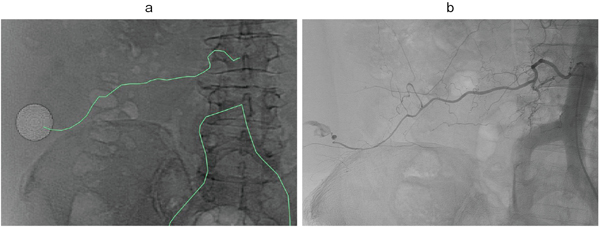

図1 仮想透視画像(Virtual Fluoroscopy)

右第3腰動脈遠位からの出血症例。仮想透視画像(a)では、CTにてExtravasationを認めた位置を丸で囲み、同部に向かう責任血管の走行をパス(緑のライン)で示している。L3棘突起上縁右側より起始していることがわかる。実際の血管撮影画像(b)と酷似していることがわかる。